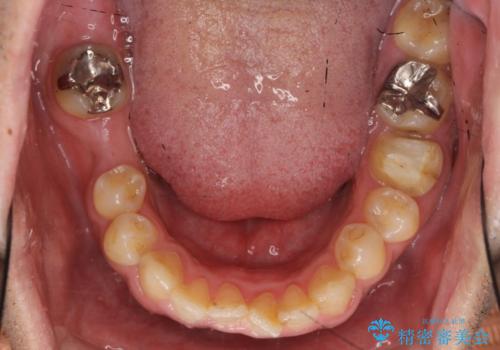

- 40代男性

- 右下の奥歯にインプラントを入れたいと来院。

抜歯から時間が経っており、骨が十分あったためすぐにインプラントを入れることが可能でした。骨も補う必要がありませんでした。

インプラント手術時に同時に親知らずの抜歯も行い、腫れや痛みなどを1度で終わらせるようにしました。